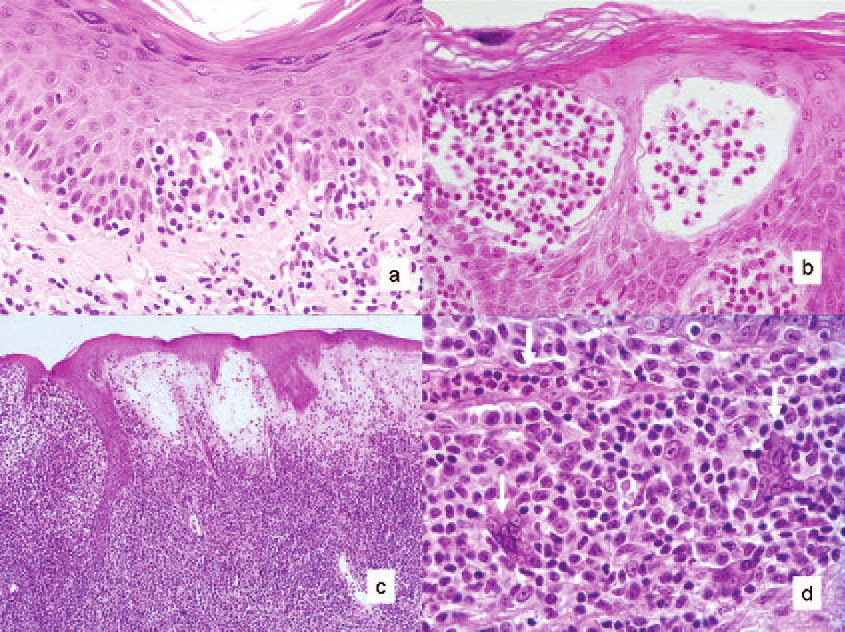

Mycosis Fongoïde =التفطر الكمئي